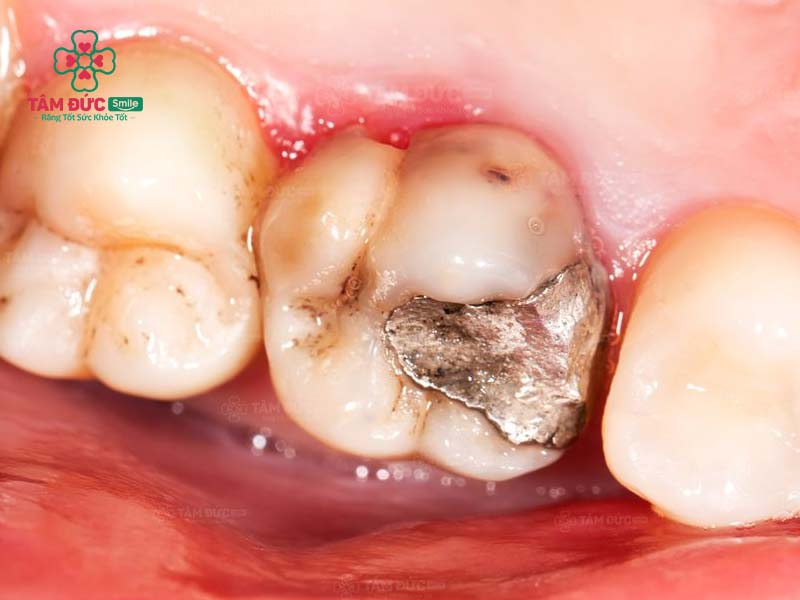

1.4. Thay miếng trám mới

Hiệu quả trám răng không thể duy trì vĩnh viễn. Theo thời gian, miếng trám răng cũ có thể bị bong tróc hoặc rơi ra do tác động từ lực ăn nhai. Trong trường hợp này, bác sĩ sẽ yêu cầu thay miếng trám răng mới.

Quý khách cần trám lại răng khi miếng trám cũ bị bong tróc